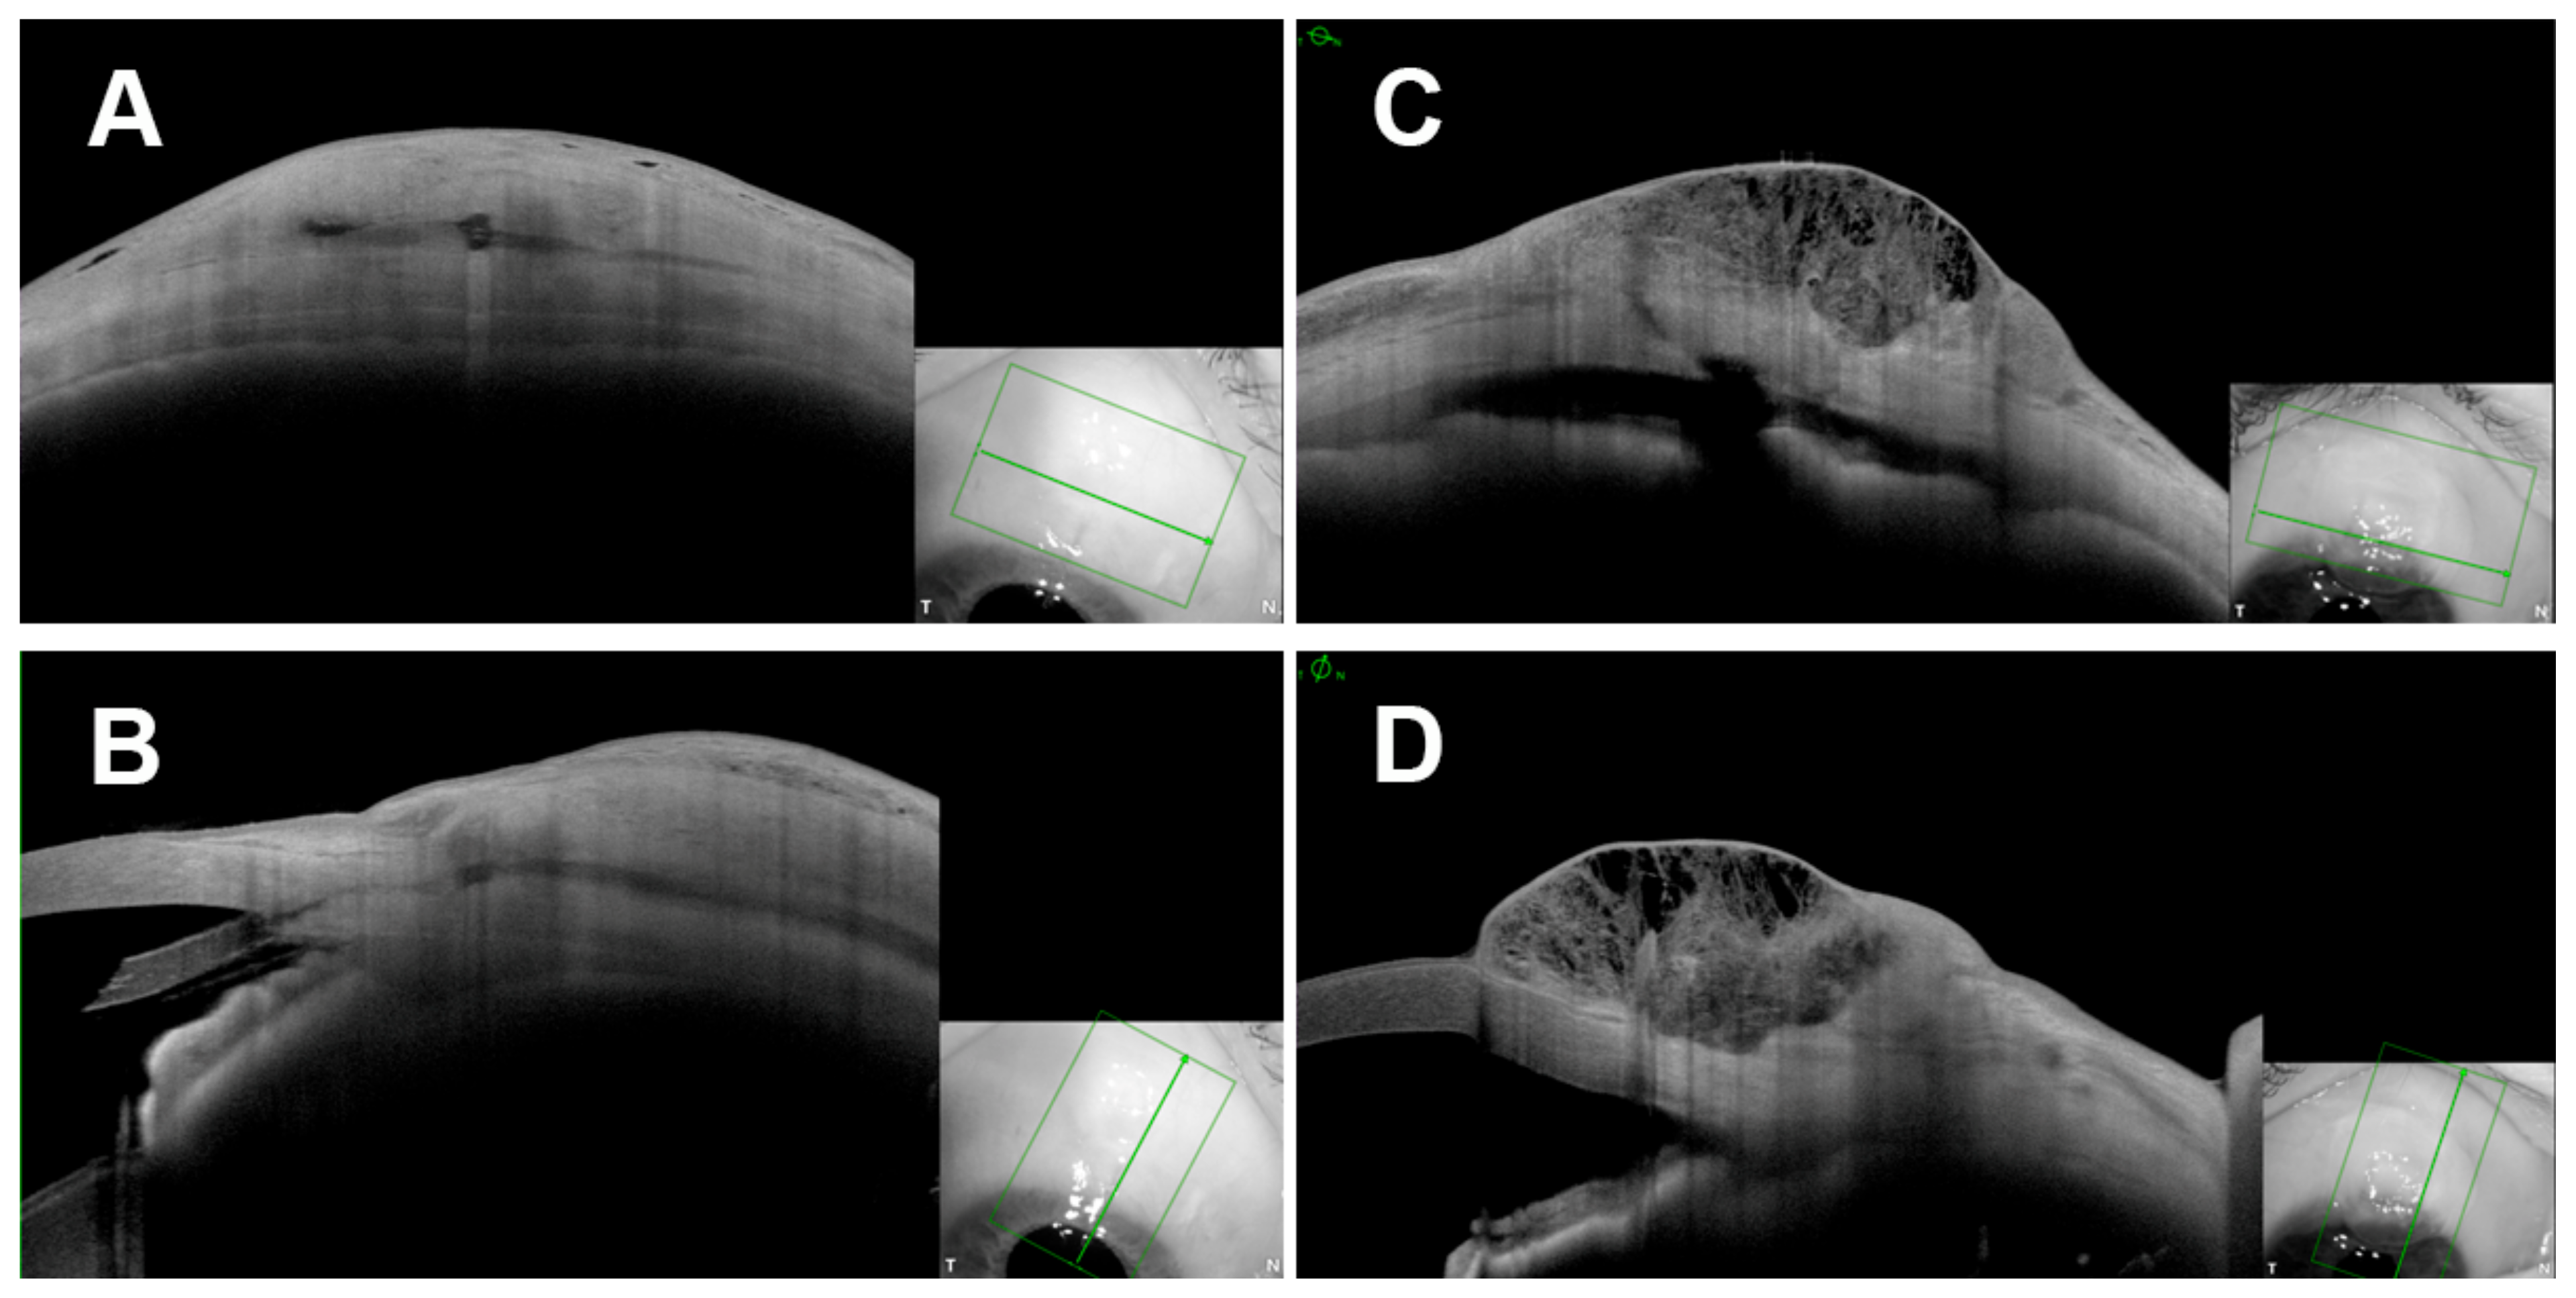

| Morphological Pattern | PRESERFLO-Group | Trabeculectomy-Group | p Value |

|---|---|---|---|

| C0 | 5 (8.8) | 2 (5.5) | 0.5 |

| C1 | 2 (3.5) | 8 (22.2) | 0.007 |

| C2 | 46 (80.7) | 26 (72.2) | 0.086 |

| T0 | 0 (0) | 0 (0) | - |

| T1 | 16 (28.0%) | 5 (13.8) | 0.084 |

| T2 | 32 (56.1) | 20 (55.5) | 0.727 |

| T3 | 6 (10.5) | 11 (30.5) | 0.021 |

| ES1 | 50 (87.7) | 28 (77.8) | 0.1 |